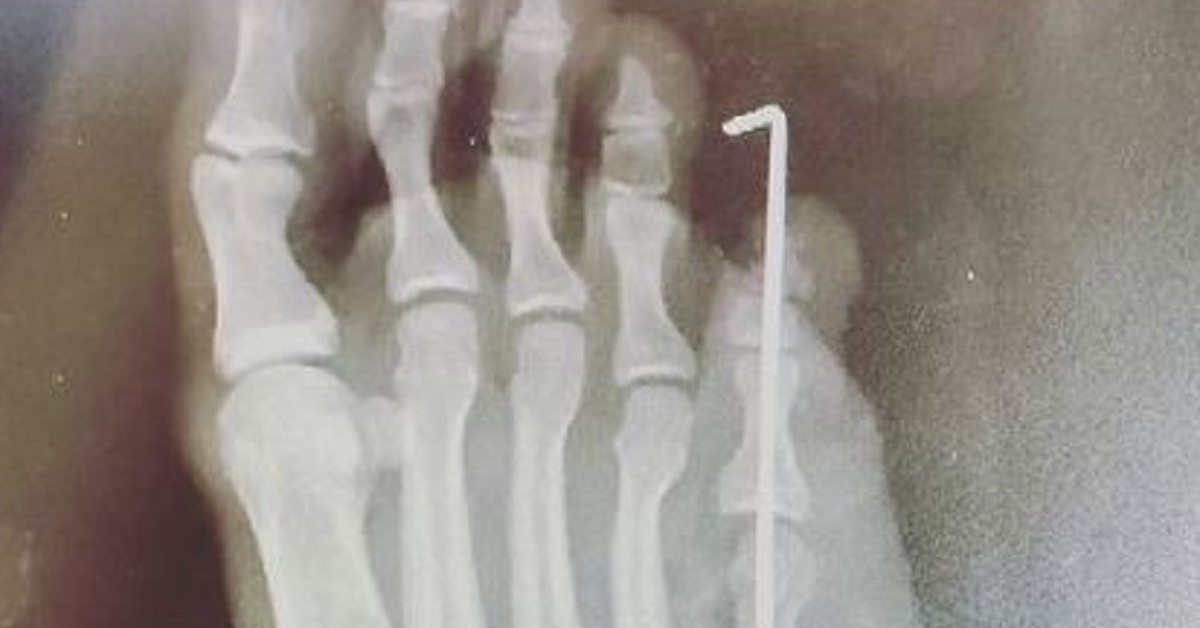

「もし今月がダメだったら、体外受精します」とのこと。